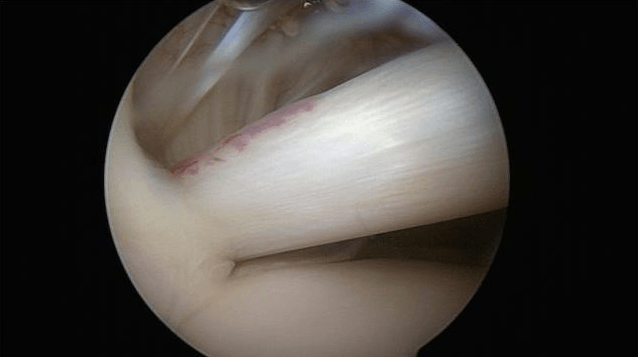

El rodete glenoideo es un fibrocatílago que contribuye a la estabilidad pasiva de al articulación gleno-humeral, junto con la cápsula y la superficie articular. Sobre la parte superior del mismo se inserta el tendón de la porción larga del bíceps, que se hace intraarticular.

Conviene realizar un artro-escáner para localizar la lesión, aun así, solamente se detectan el 45% de los casos. Solamente la artroscopia exploratoria permite realmente realizar un examen de la articulación.

El tratamiento es esencialmente quirúrgico y varía en función del tipo de lesión:

- Bien una resección del rodete dañad

- Bien una reinserción del rodete